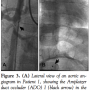

Failures (Table 2; Figures 1 and 2). Overall, there were 6 failures in 6 patients (4.3%): 3 recovered failures (2.1%), and 3 definite failures (2.1%). There were no failures in the coil group, 3 failures in the ADO I group (1 recovered), and 3 failures in the ADO II group (2 recovered).

For the ADO I, immediate closure was achieved in 40% of the cases (30/74 patients), rising to 94.6% (70/74 patients) at 24 hours, and to 96% (71/74 patients) at 6 months. Thus, the ADO I failed to close the PDA in 3 patients. The first patient (Patient 1 in Table 2 and Figure 1) was a 3-year-old, 17 kg boy with a 4 mm type D PDA which was initially closed with an 8-6 ADO I. The Amplatzer asymptomatically migrated to the abdominal aorta before discharge from the hospital. The shunt seen on the follow-up serial echocardiograms was thought to

be a residual shunt, and the migration was diagnosed only 1 year later. We believe that this migration occurred on the second day, because the predischarge chest x-ray examined retrospectively 1 year later did not show the radio-opaque markers of the ADO in the usual position. The device was embedded asymptomatically in the abdominal aorta, facing the celiac artery (Figure 3A, black arrow). Attempts at its percutaneous removal 1 year later failed due to strong adhesions to the aortic wall; hence, it was left in place since it wasn’t obstructive. This failure was considered recovered, as the PDA was percutaneously closed using a 14-12 ADO I (Figure 3B); the device was oversized to achieve incomplete deployment of the aortic disc inside the PDA (Figure 4). The first ADO is still in the abdominal aorta with no gradient on the serial Doppler studies for 6 years now. The second patient (Patient 2 in Table 2 and Figure 1) was a 7-month-old who weighed 6.5 kg, with a 2.2-mm wide and 9-mm long type C PDA. When it was advanced and correctly positioned in the PDA, the 6-4 ADO I became severely kinked with a very narrow angle, and thus kept sliding backward and protruding into the pulmonary artery during every release attempt. The device wasn’t released, the procedure was abandoned, and the patient was referred for surgery 3 months later. This happened before the ADO II era. The third ADO I failure (Patient 3 in Table 2 and Figure 1) was a 6-month-old, 7 kg baby girl with a type B, 6.6 mm duct; the 10-8 ADO I totally obstructed the aortic flow and was retrieved before releasing. The patient was also referred for surgery.